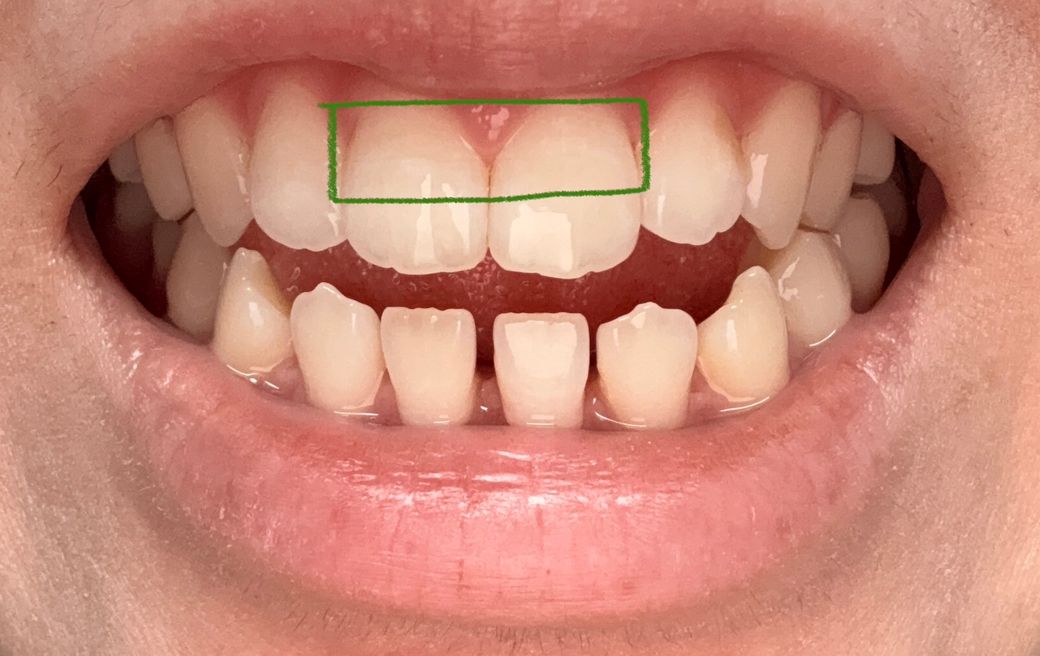

우연히 양치를 하나 봤는데 위 앞니양쪽 에 가로 금이 있더라구요 ㅠㅠ 특히 오른쪽이 좀더 진하구요(사진상은 반대에요) 그냥 외관상 봤을때는 첫번째 사진 파란 네모안에 처럼 좀 금이 살짝 보이는정도고 각도에 따라서 두번째 사진에 보라색 네모친 부분처럼 그림자처럼 보이기도해요 근데 확실히 플래쉬를 비추면 세번째 사진 초록색 네모부분안에 금이 훨씬 잘보여요 ㅠㅠ 혹시나해서 안쪽도 보니 금이 살짝있는데 바깥 금이랑은 같은 위치인지는 모르겠는데 네번째 사진상으로 안나와서 대충 그려서 올립니다! 검은 색 선처럼 약간 가로금이있어요 그런데 제가 원래부터 앞니에 세로로 된 실금은 좀 있었는데 가로로 된 실금은 처음봤어요 ㅠㅠ 그동안 앞니에 큰 충격은 따로 없었고 있어봤자 양치하다 칫솔에 앞니 부딪히는정도가 끝이었어요 몇주전 한번 금있는 치아가 갑자기 시리거나 물 닿았을때 시린건 한번씩 있었는데 그 뒤로는 불편한 건 없었고 금이 만져지거나 하지도않아요 그리고 무엇보다 이번년도 4월에 정기검진했는데 엑스레이도 촬영했는데 이때도 치아 금은 보이지않는다 그러셨거든요 ㅠㅠ 혹시몰라 마지막사진 첨부합니다 이때 금이 있었는지는 모르겠으나 이상없다하셨는데 외상이 없는데 갑자기 금이 생길수 있나요…? 제가 근데 개방교합이라 윗니들이 간격이 좁아서 살짝 튀어나오고 뒤틀어진건 있습니다 ㅠㅠ 일단 사진 보시기에 치료가 필요한 수준인가요..?😭 임플란트 해야할까봐 무서워요 ㅠㅠ 꼭 답변 부탁드릴게요..

• 3번 째 사진